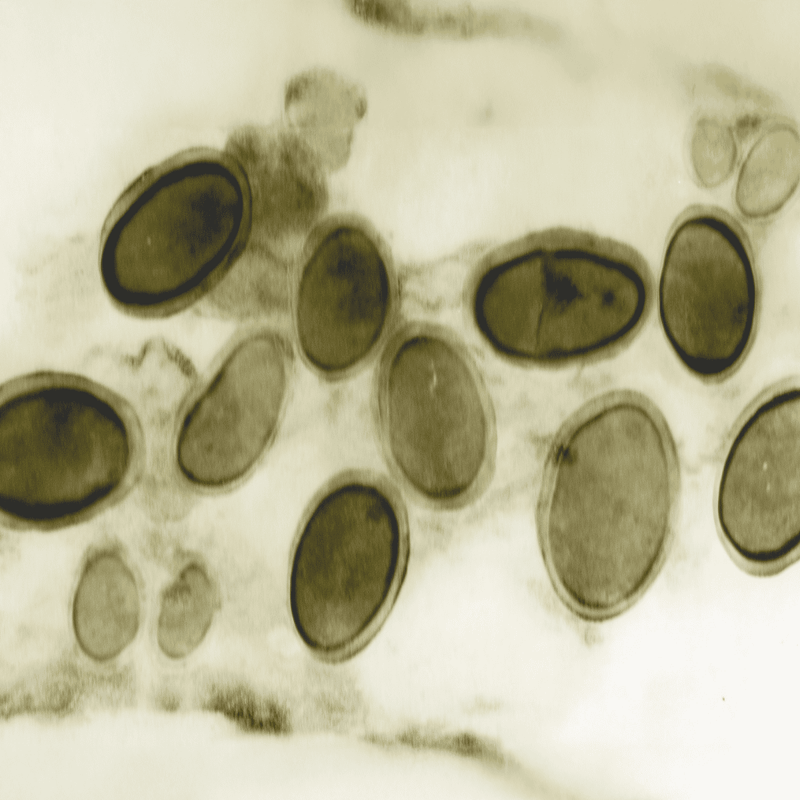

Ear mites are tiny parasites that live in a dog’s ear canal. The life cycle of ear mites consists of four stages: egg, larva, protonymph, and adult.

Egg Stage

Ear mite eggs are laid in the ear canal. These eggs are very small and difficult to see with the naked eye. They take about 4 days to hatch.

Larva Stage

Once the eggs hatch, they become six-legged larvae. At this stage, they start to feed on ear wax and oils in the ear canal. This stage lasts for about 3-10 days.

Protonymph Stage

After the larva stage, they molt into eight-legged protonymphs. This stage also involves feeding and lasts a few more days. During this time, the mites continue to grow.

Adult Stage

The protonymphs molt again into adult mites. Adult ear mites can live for up to two months. They continue to reproduce, laying more eggs and starting the cycle anew.

Understanding these stages is key to treating ear mites effectively. Treatment usually targets both the adult mites and the eggs to stop the cycle. It is important for pet owners to follow veterinary advice to ensure complete eradication.